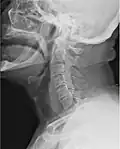

Beeldvormend medisch onderzoek van de menselijke keel waarbij gebruik wordt gemaakt van röntgenstraling.